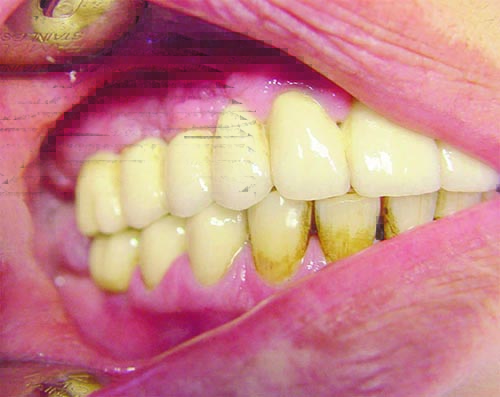

Right view, occlusion mandibulе teeth

Left view. The nicotine deposit on the teeth is clearly visible on both pictures. Those picture have played a good motivational role, so that the patient to quit smoking.

Here is the result from heavy smoking and poor oral hygiene. Another case in my practice.